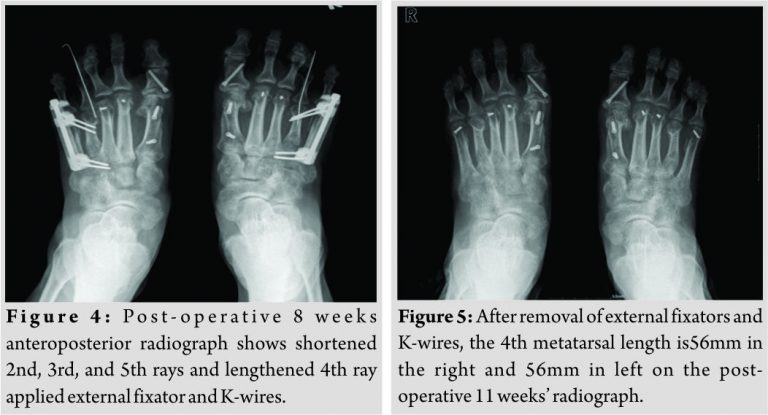

Length of each metatarsal is described in [Table 1]. At first, we did scarf and akin osteotomy under spinal anesthesiafor correcting hallux valgus and lowering the first metatarsal, and then the osteotomy site was fixed by two Barouk screws (Depuy S.A., Lyon, France).Then,Weil osteotomy was performed on the second, third, and fifth metatarsals to shorten adjacent metatarsals. For callotasis, we placed an external fixator (Mini fixator, Orthotech, Korea) on the fourth metatarsal, and then did osteotomy after longitudinal incision on the proximal part of the metatarsal shaft. To maintain the alignment of the interphalangeal joint and prevent the flexion deformity of the metatarsal head, K-wire was inserted from the distal phalanx to the distal part of the metatarsal (Fig. 3). She started a passive range of motion exercise 3 day after surgery. On 7 days after surgery, she wore a special foot brace, which help to walking just using hind foot, and start partial weight-bearing. The goal of the 4th metatarsal bone was to target 56 mm to be located on the proximal side of the 6 mm with the 3rd metatarsal head shortened after Weil osteotomy was performed. From the 10th day to the 7th week after the surgery, we sought to extend the length of 5mm 2–3 times a day. After the 8th week after surgery, the length remained the same (Fig. 4), then the external fixator was removed after confirming of callus formation at the post-operative 11th week (Fig. 5).